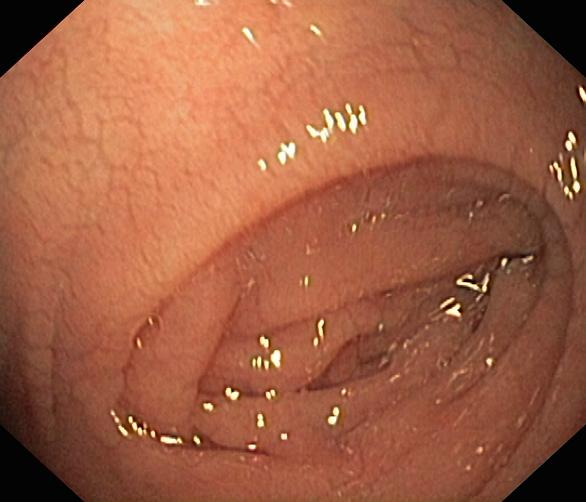

Celiakia